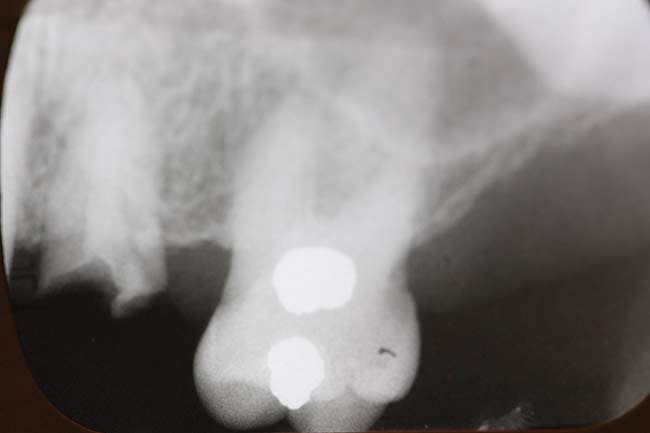

In a similar case, a 45-year-old man presented with tooth No. 13 fractured 2 years after having a porcelain crown made (Figure 4). His dental condition was excellent with only five amalgam fillings in his mouth. He was interested in an immediate replacement because he felt uncomfortable chewing without this tooth. He had considered a fixed bridge but was reluctant to prepare the two adjacent teeth, which had very small amalgams in them. He elected to have the root extracted and an immediate implant placed. Figure 5 is an x-ray of a 4.3-mm Hiossen implant placed with a torque of 60 newton centimeters and restored with a provisional abutment. After the patient felt the bite was comfortable, a final crown with a screw-retained single-piece crown and abutment (Figure 6) was inserted. The x-ray pictured is 2 years post-insertion with no bone loss visible. The implant has maintained the same alveolar bone level since placement and appears stable due to the platform-switch placement of the abutment.